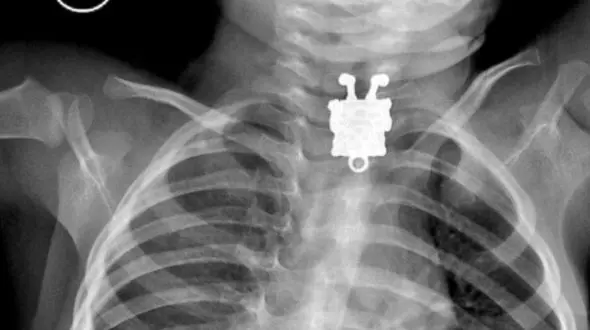

رکنا: پزشکان عربستانی در جراحی موفقیتآمیزی یک سنجاق فلزی را از گلوی نوجوان 16 سالهای بیرون کشیدند.